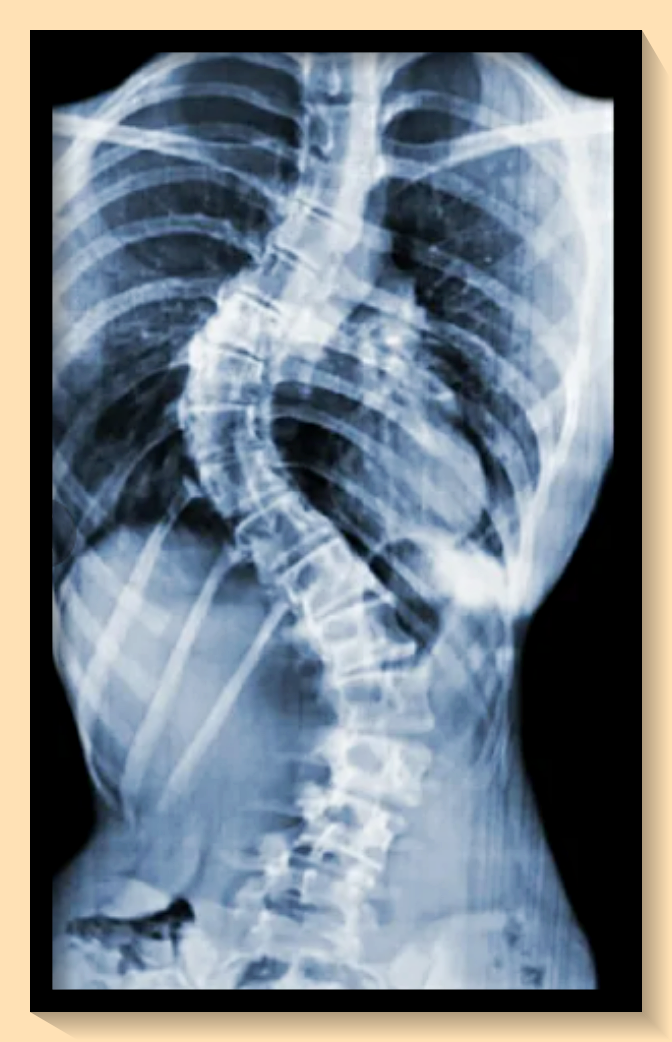

척추측만증이란 척추가 곧게 서 있지 않고 한 쪽으로 휘어져 있는 상태를 지칭하는데요, 이는 우리가 생각하는 것보다 더 심각한 건강 문제를 야기할 수 있습니다. 척추의 변형이 심해질수록 주변 장기에 압박이 가해져 기능 장애가 발생할 수 있답니다.

병역 신체검사에서 척추측만증의 판정을 이해하기 위해서는 '콥각도'라는 개념을 알아야 합니다. 병역 판정에 따라 등급이 달라집니다. 2024년부터는 20도 이상 40도 미만의 척추측만증 환자는 3등급으로 분류되어 현역 복무 대상이라는 새로운 기준이 적용되었습니다. 40도 이상의 경우에는 공익 판정을 받을 수 있습니다. 병무청에서는 X-ray 장비로 체크를 하지만, 병원에서 받은 서류를 준비해 가는 것이 좋습니다.